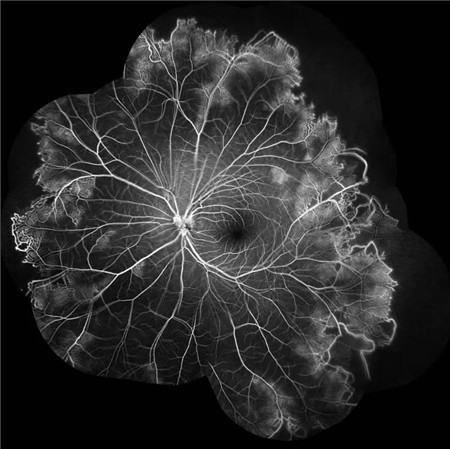

经过详细的眼底检查后,患者被诊断为IRVAN综合征引起的右眼黄斑裂孔,张风院长带领医生团队为患者施局右眼玻璃体切除+剥膜+眼内光凝+气液交换手术,经过半个月的恢复,患者右眼术后视力由术前0.3-达到0.6-的状态,且裂孔呈逐渐闭合状态。

静脉不规则扩张和血管鞘膜,周边部小血管广泛闭塞,交界处毛细血管扩张和异常吻合。

严重者可发生从周边到黄斑的血管闭塞和缺血、玻血、新生血管性青光眼,最终视神经萎缩。